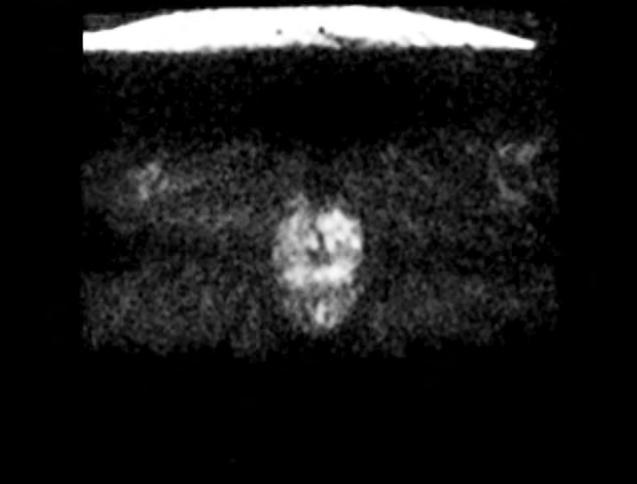

Morphologisches T2-Bild (oben) und Diffusionsbild (DWI, unten) mit tumorverdächtigen Arealen (rot) links in der hinteren peripheren und vorderen Transitionalzone der Prostata.

Die radiologische Untersuchung umfasst eine hochauflösende, morphologische MRT der Prostata in mehreren Ebenen, eine Perfusionsbildgebung (Durchblutungsmessung) mit KontrastmittelInjektion, sowie eine Diffusionsbildgebung (DWI) zur Beurteilung der Molekularbewegung des Gewebes. Erst die Kombination dieser MRT-Techniken an einem hochauflösenden 3-Tesla-MRT ermöglicht es, den Krebs in der naturgemäß „unübersichtlichen“ Prostata (vergrößert, knotig, verkalkt) zu entdecken. Die Bildanalyse erfolgt in Form einer

strukturierten Befundauswertung nach dem aktuellen PIRADs–Standard, der die Kommunikation zwischen Ärzten erheblich verbessert.